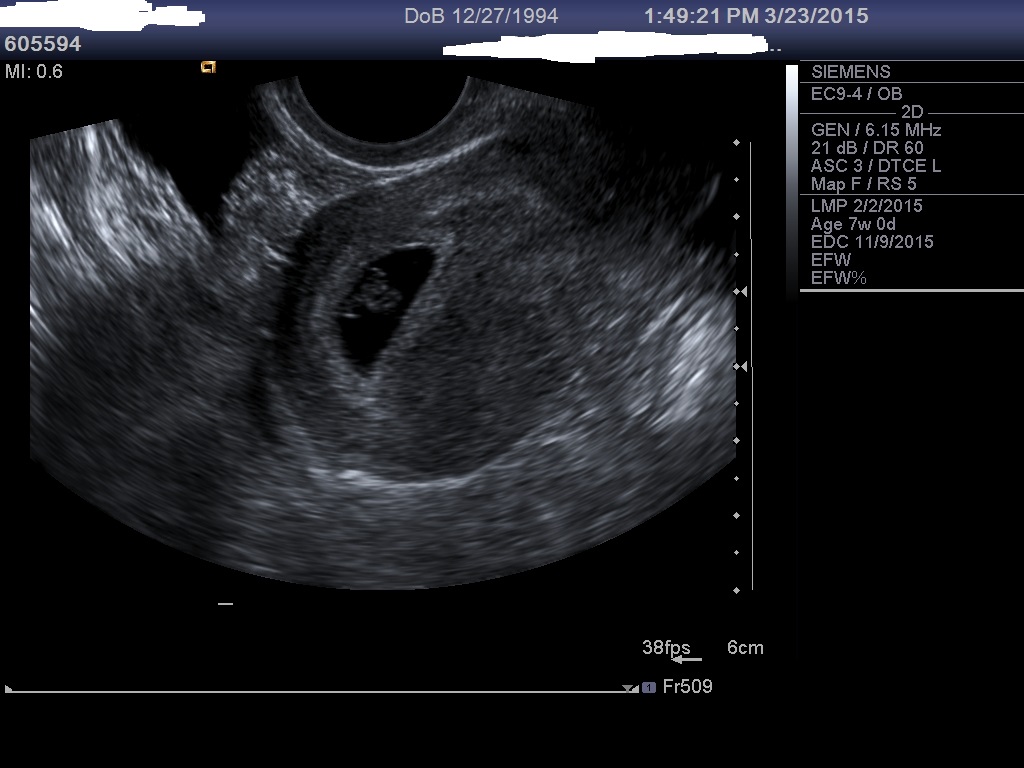

Two pics of the u/s at 7 weeks: